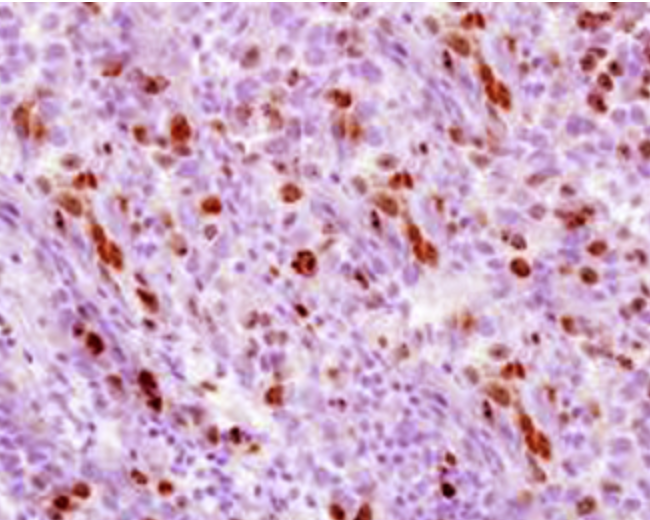

Фотографии опухоли медуллярной аденокарциномы

Раздел: Снимки-откровения